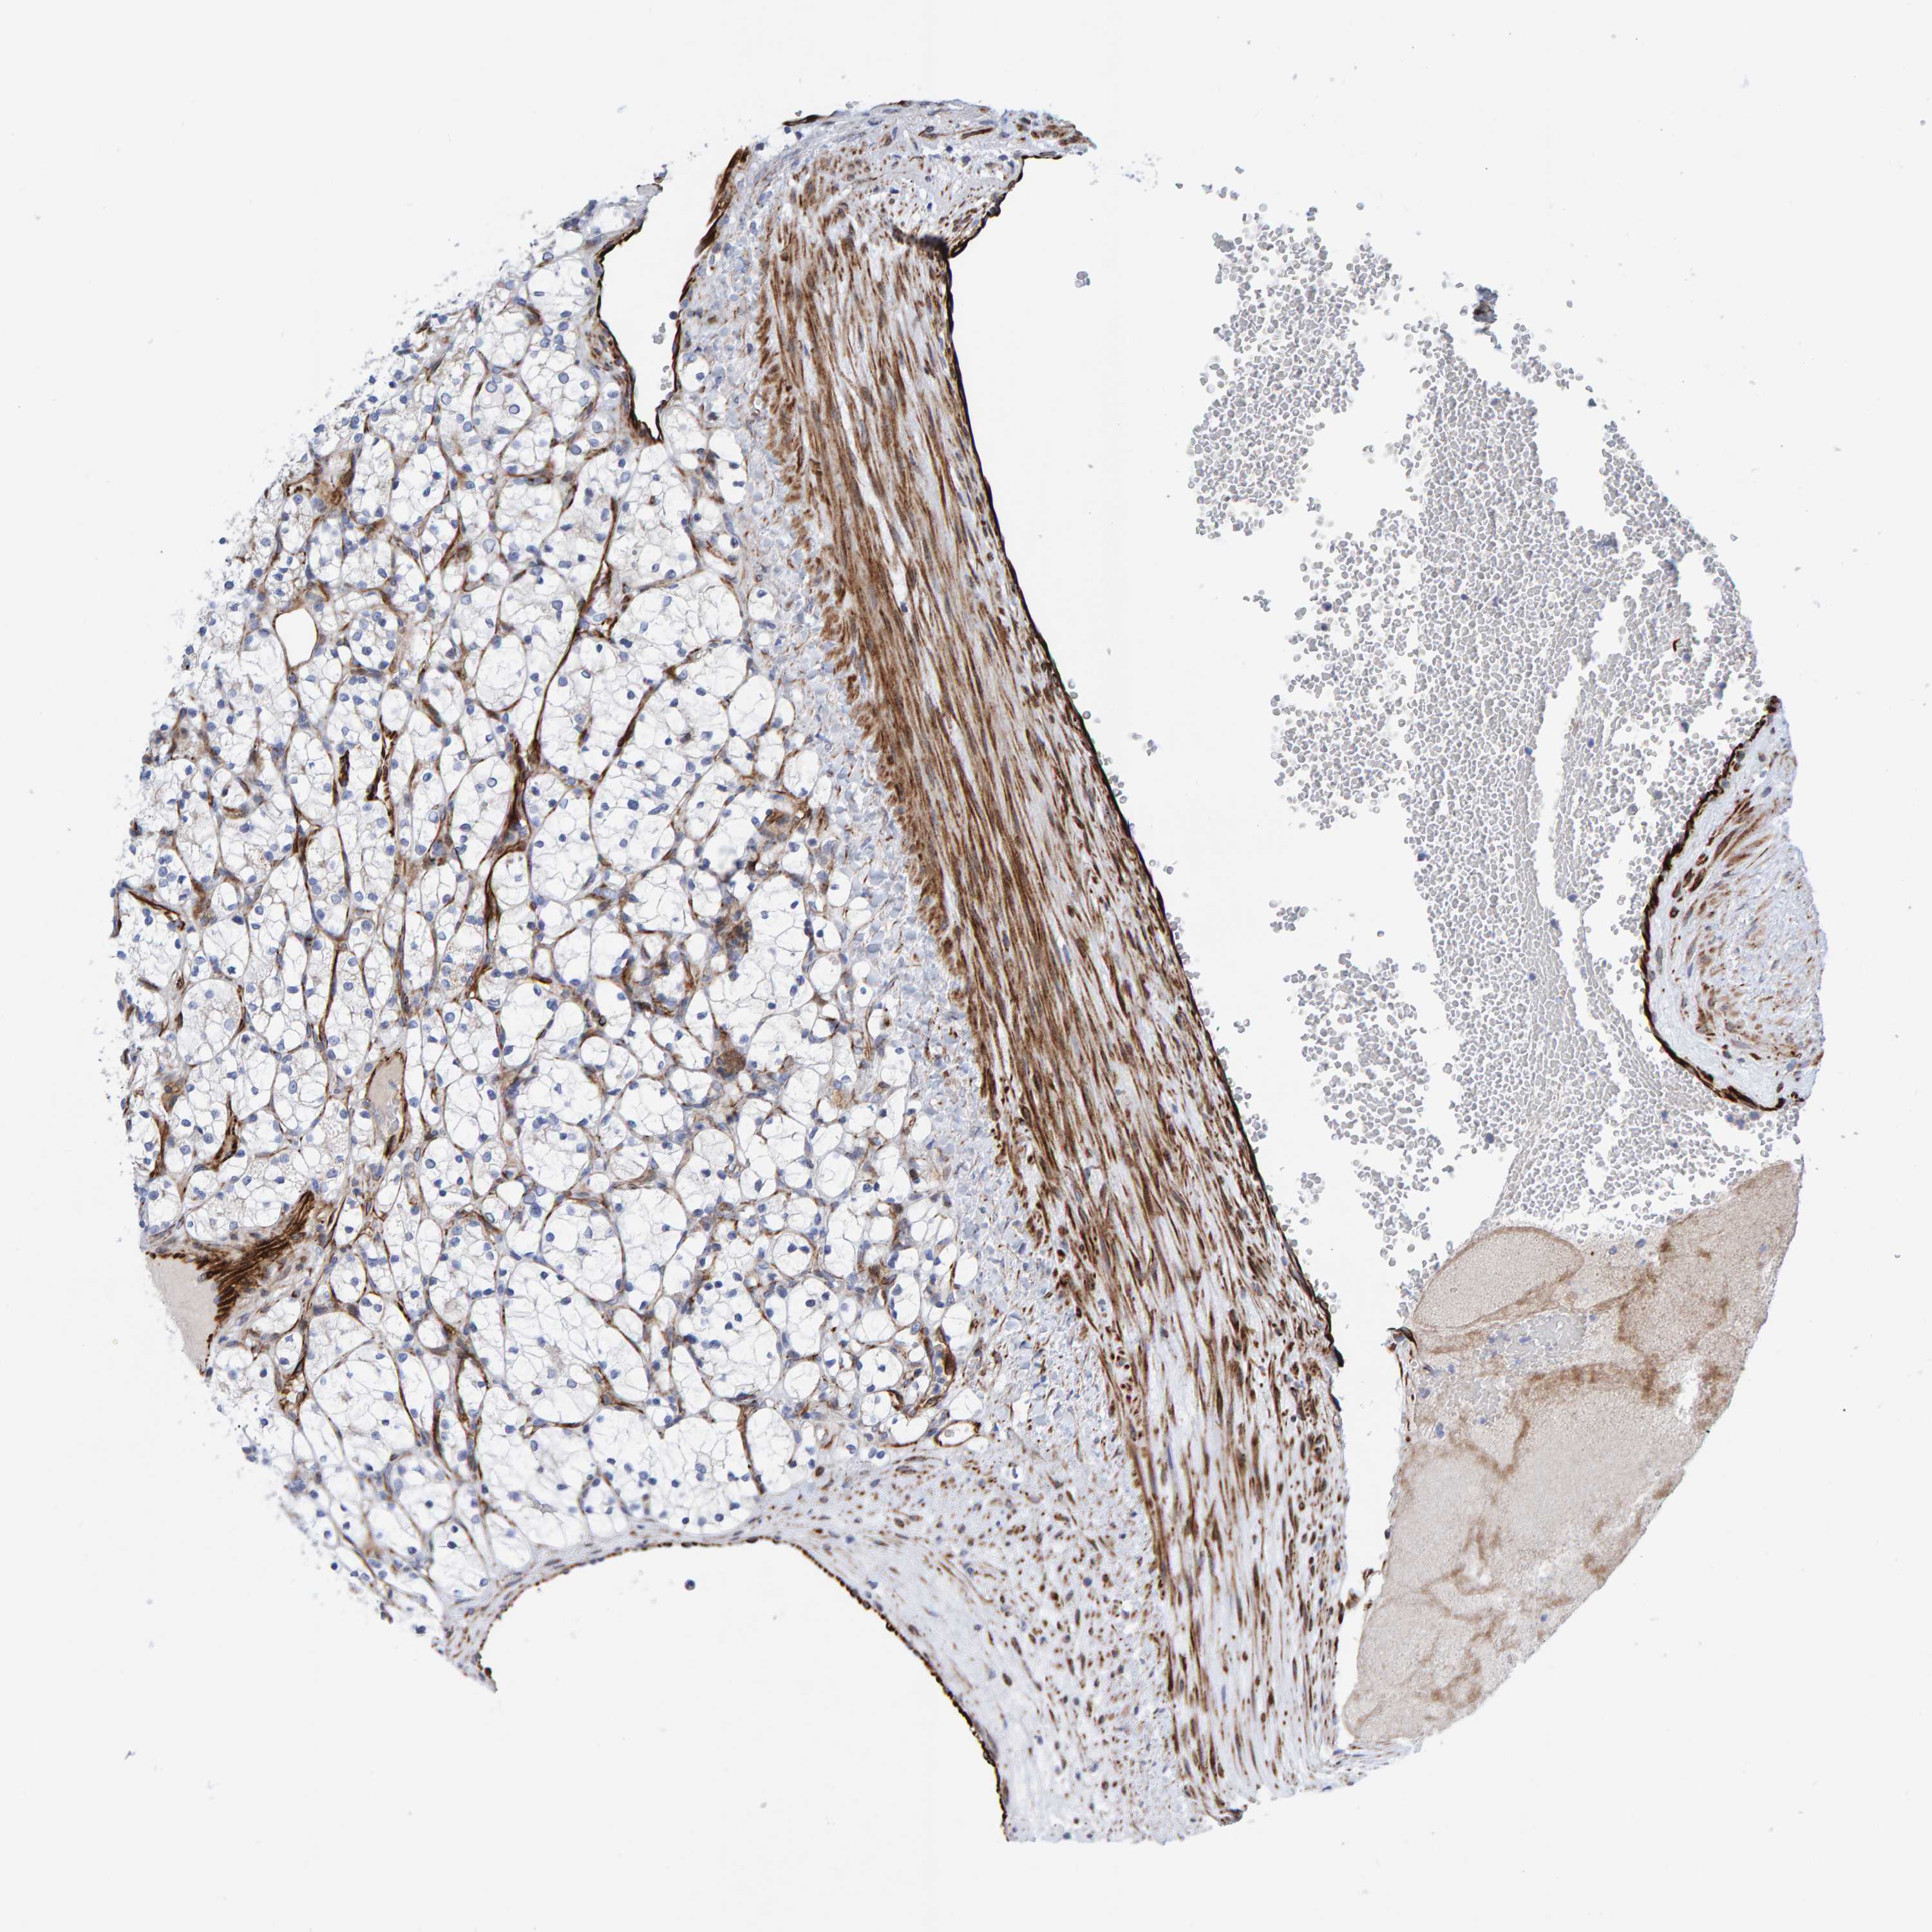

Renal cancer

Kidney renal papillary cell carcinoma